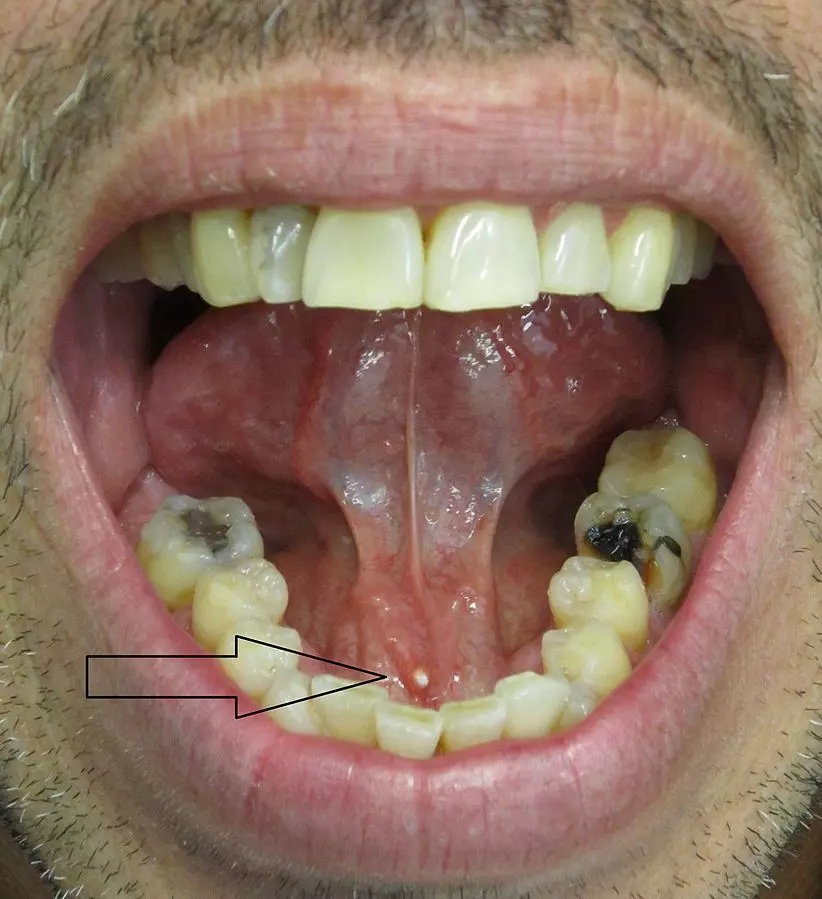

Sialolithiasis is the medical term for stones in the salivary glands or the salivary ducts that pass saliva from the glands into the mouth. The calculi (stones) are mainly composed of calcium phosphate but can contain a variety of other compounds such as urate. The calculi can be formed in any salivary gland; submandibular (most common), parotid or sublingual.

Image - Patient with submandibular sialolithiasis

Creative commons source by James Heilman, MD [CC BY-SA 4.0 (https://creativecommons.org/licenses/by-sa/4.0)]